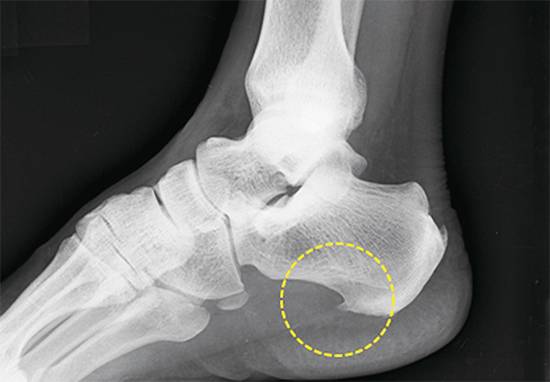

통증은 주로 발꿈치 안쪽에서 생긴다. 발가락을 발등 쪽으로 구부리면 고통이 심해지기도 한다. 가만히 있을 때는 괜찮지만 움직이면 통증이 발생하고 다시 일정 시간이 지나면 고통이 완화되는 것도 대표적인 증상이다. 통증이 가라앉았다고 해서 방심하다가는 병을 더 키울 수 있는 만큼 주의해야 한다. 족저근막 손상이 심해지면 발에 ‘골극’(사진)이 발생한다. 뼈에 붙어 있는 근막 장력 때문에 종골 부위에 뼈가 가시처럼 돋아나게 된 것. 이 경우 제거 수술까지 받아야 하기 때문에 초기 관리와 치료가 중요하다.